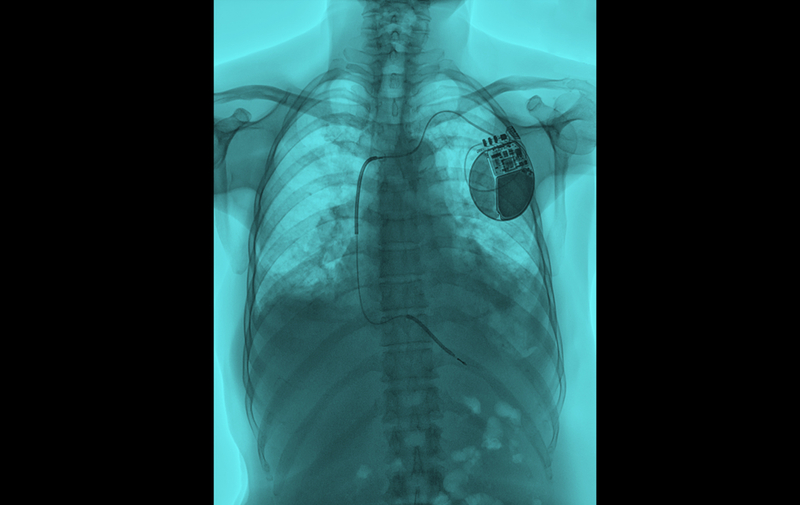

The Optimizer Smart system is comprised of several components, including an implantable pulse generator, battery charger, programmer, and software. The pulse generator is implanted under the skin in the upper left or right area of the chest and connected to three leads that are implanted in the heart. After the device is implanted, a physician tests and programs the device, which delivers electrical impulses to the heart during regular heartbeats to help improve the heart’s squeezing capability.